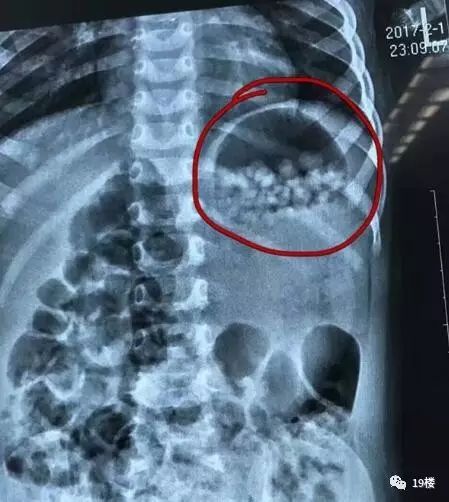

小欣来时没有明显异样,这说明水宝宝在其体内还没有膨胀到一定地步”,据该院儿科副主任医师夏顺林介绍,当他看到为小欣检查所拍的片子时,着实吓了他们一条,胃里面都是密密麻麻的球状物体,因为就医及时,院方建议保守治疗,即通过药物促进小欣的肠蠕动,然后自行排出,果不其然,服用药物后,当天夜里,小欣就排出10多颗已开始膨胀的“水宝宝”,小欣每次排便后,她的家人都会用手机拍下来,然后把照片放大,仔细数排出的“水宝宝”颗数。

截至3日中午,小欣体内的“水宝宝”已排出200多颗,剩余的估计在24小时内能全部自行排出